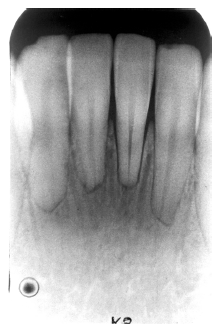

Figure 2 - Advanced Enamel Caries

Figure 2

While advanced dental caries may well involve the entire tooth, early or incipient caries involves only the enamel. Once a carious lesion penetrates through the enamel, it is usually considered to be dentinal caries. Clinically, enamel caries usually appears as a stained system of occlusal grooves or as chalky white bands along the labial/buccal gingival aspects of the teeth. Radiographically, enamel caries is characterized by a focal loss of the normal enamel radiopacity, particularly on the interproximal surfaces.

It appears as a radiolucent cone shape, with the base at the exterior surface and the tip of the cone toward the pulp. The lesion follows the enamel rods. After progression into the dentin the lesion usually takes on a radiolucent fan shape.

To be detectable on a radiographic image there must be a 30% to 50% change in the mineral content of the enamel lesion. Less than 30% demineralization will not produce a detectable image. The advancing edge of the lesion may not be 30% demineralized and thus will appear smaller in the radiographic image because the rest of the advancing edge is not radiographically visible. Clinically the lesion will usually be larger than its radiographic image.

Figure 2 illustrates advanced enamel caries on the mesial surface of the premolar.